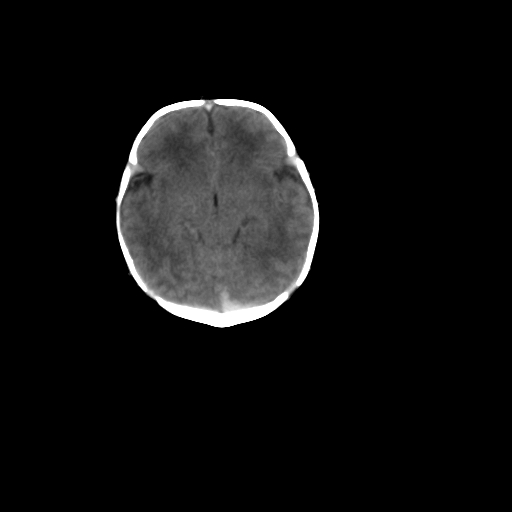

男,12天,自然分娩,其母发现右顶部头皮包块逐渐增大。

右顶部头皮血肿

右顶骨呈膨胀性改变,骨纤维结构不良?

右顶部头皮血肿,可能是产道挤压所致。以后会慢慢恢复。

疑问:患儿脑白质密度比较低,基底节区密度比较高,类似于“双圈征”脑沟密度也偏高。该婴儿可有别的异常吗?反射正常吗?评分能达到5分吗?如果正常,就随诊观察吧。不正常要考虑到缺血缺氧性脑病。